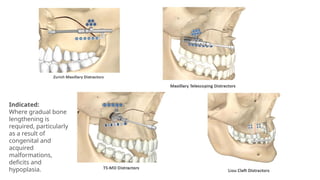

Indicated:

Where gradual bone

lengthening is

required, particularly

as a result of

congenital and

acquired

malformations,

deficits and

hypoplasia.